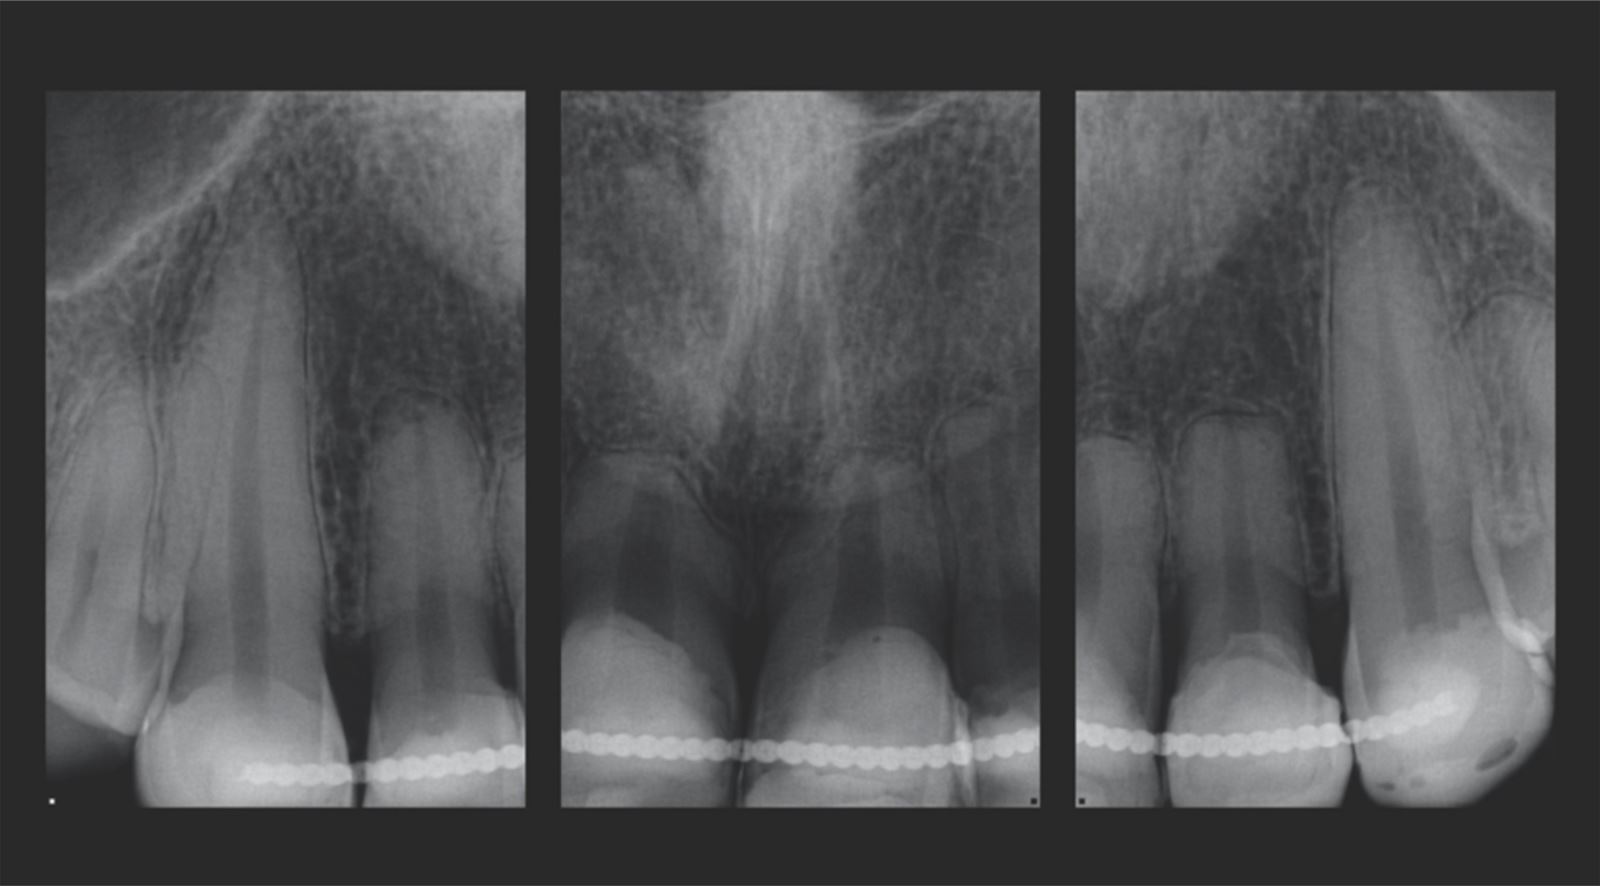

Mladá žena ve věku kolem 20 let, kterou trápila diskolorace horních frontálních zubů po dřívějším traumatu, vyhledala ošetření u Dr. Jaleeny Fischer-Jessop, DDS, MBA. Hledala řešení, které by obnovilo její úsměv. Pacientka byla ošetřena konzervativní a cenově dostupnou metodou: kompozitními fazetami bez preparace, přímým bondingem. Dr. Fischer-Jessop zvolila tento postup k překrytí diskolorace a sjednocení horních zubů s dolními frontálními – bez nutnosti invazivnějších výkonů, jako jsou implantáty, nebo nákladných laboratorně zhotovovaných fazet. Pro zesvětlení zubů byly vybrány odstíny B1D a Enamel White (EW) a odstín Universal Body (UB) kompozitu Transcend™ byl použit k přirozenému splynutí okraje v cervikálních oblastech.

Pacientka ve 20 letech s anamnézou traumatu horních frontálních zubů. Přestože trauma proběhlo, zuby zůstaly stabilní, takže implantáty nebyly nutné.